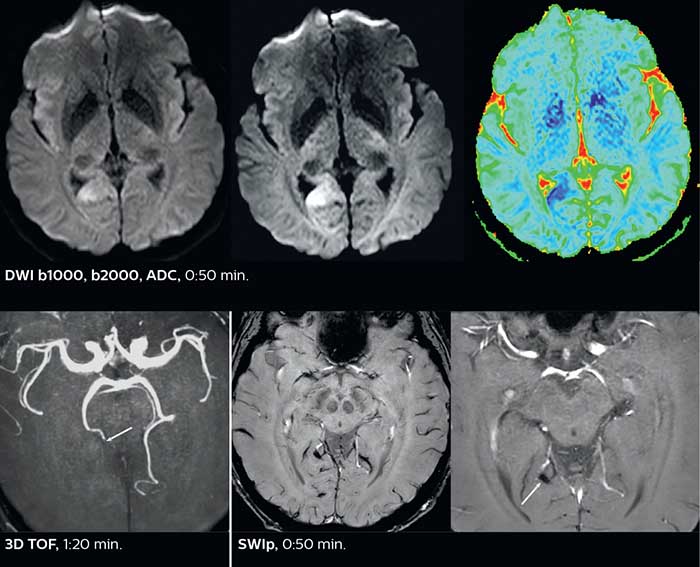

Dr. Savatovsky appreciates the improvements and flexibility that Elition with Compressed SENSE and MultiBand SENSE provides, particularly for stroke patients. “For stroke, it allows us to cut about 5 minutes off of our stroke protocol, or to keep the same acquisition time and get more insights.” The ability to perform more sequences can help in making a swift and confident diagnosis. “For example, our stroke cases usually include the regular sequences that every center does (b1000 diffusion, FLAIR, time-of-flight angiography), but we also image supra aortic vessels, and we can replace a gradient echo sequence with a fast 50-second susceptibility-weighted sequence, and all of this doesn’t add much time. because all the regular sequences are accelerated on Elition.” “The time savings with Compressed SENSE and MultiBand SENSE make it easier to add sequences to give us additional insights. Depending on the context and the first results, we might add a DSC perfusion to assess the ischemic penumbra, an ASL perfusion to help find an alternative cause in case of normal diffusion, or add a high-resolution T1 sequence for a stroke patient, to quickly assess wall imaging in emergency cases. The additional sequences can help improve patient management, because we can already consider some alternative diagnoses if the morphological MRI is normal.”

In this patient with acute right motor deficit and aphasia, the b2000 diffusion weighted image is normal. The SWIp image demonstrates more prominent veins in the right hemisphere, which could reflect increased deoxyhemoglobin contents. Fast ASL shows low CBF regions in the left frontal lobe. A follow-up ASL after one hour demonstrates high CBF values in the same area. The final diagnosis was migraine with aura.